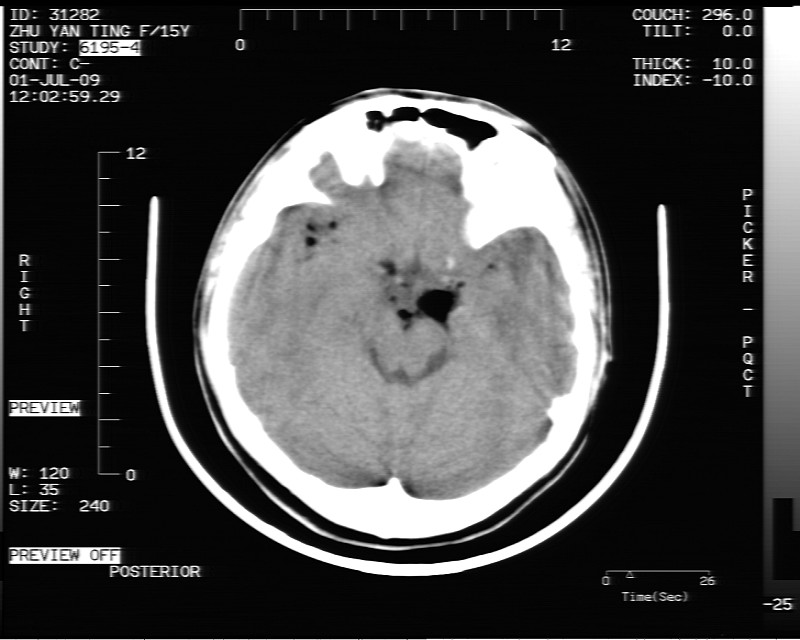

以下是引用随光逐影在2009-7-1 16:26:00的发言:[br]鞍上池表皮样囊肿或含脂肪类肿瘤破裂并化学性脑炎?

以下是引用余辉在2009-7-1 17:20:00的发言:[br]病变ct值-20至-80[br]考虑脑内脂肪瘤破裂,瘤主体应该在右侧桥小脑角池及鞍上池[br]鞍上池病灶面积较大,ct值应该能够测准,应此病灶应该就是脂肪密度,病灶密度有ct值-20至-80hu,为成熟脂肪密度,因此考虑脂肪瘤,也不除外其他含成熟脂肪的病灶[br]皮样囊肿密度应该稍高一点

以下是引用zjzjr在2009-7-1 16:52:00的发言:[br]支持皮样囊肿破裂.,表皮样囊肿一般密度均高.[br][br][本贴已被 zjzjr 于 2009-7-1 16:52:29 修改过]